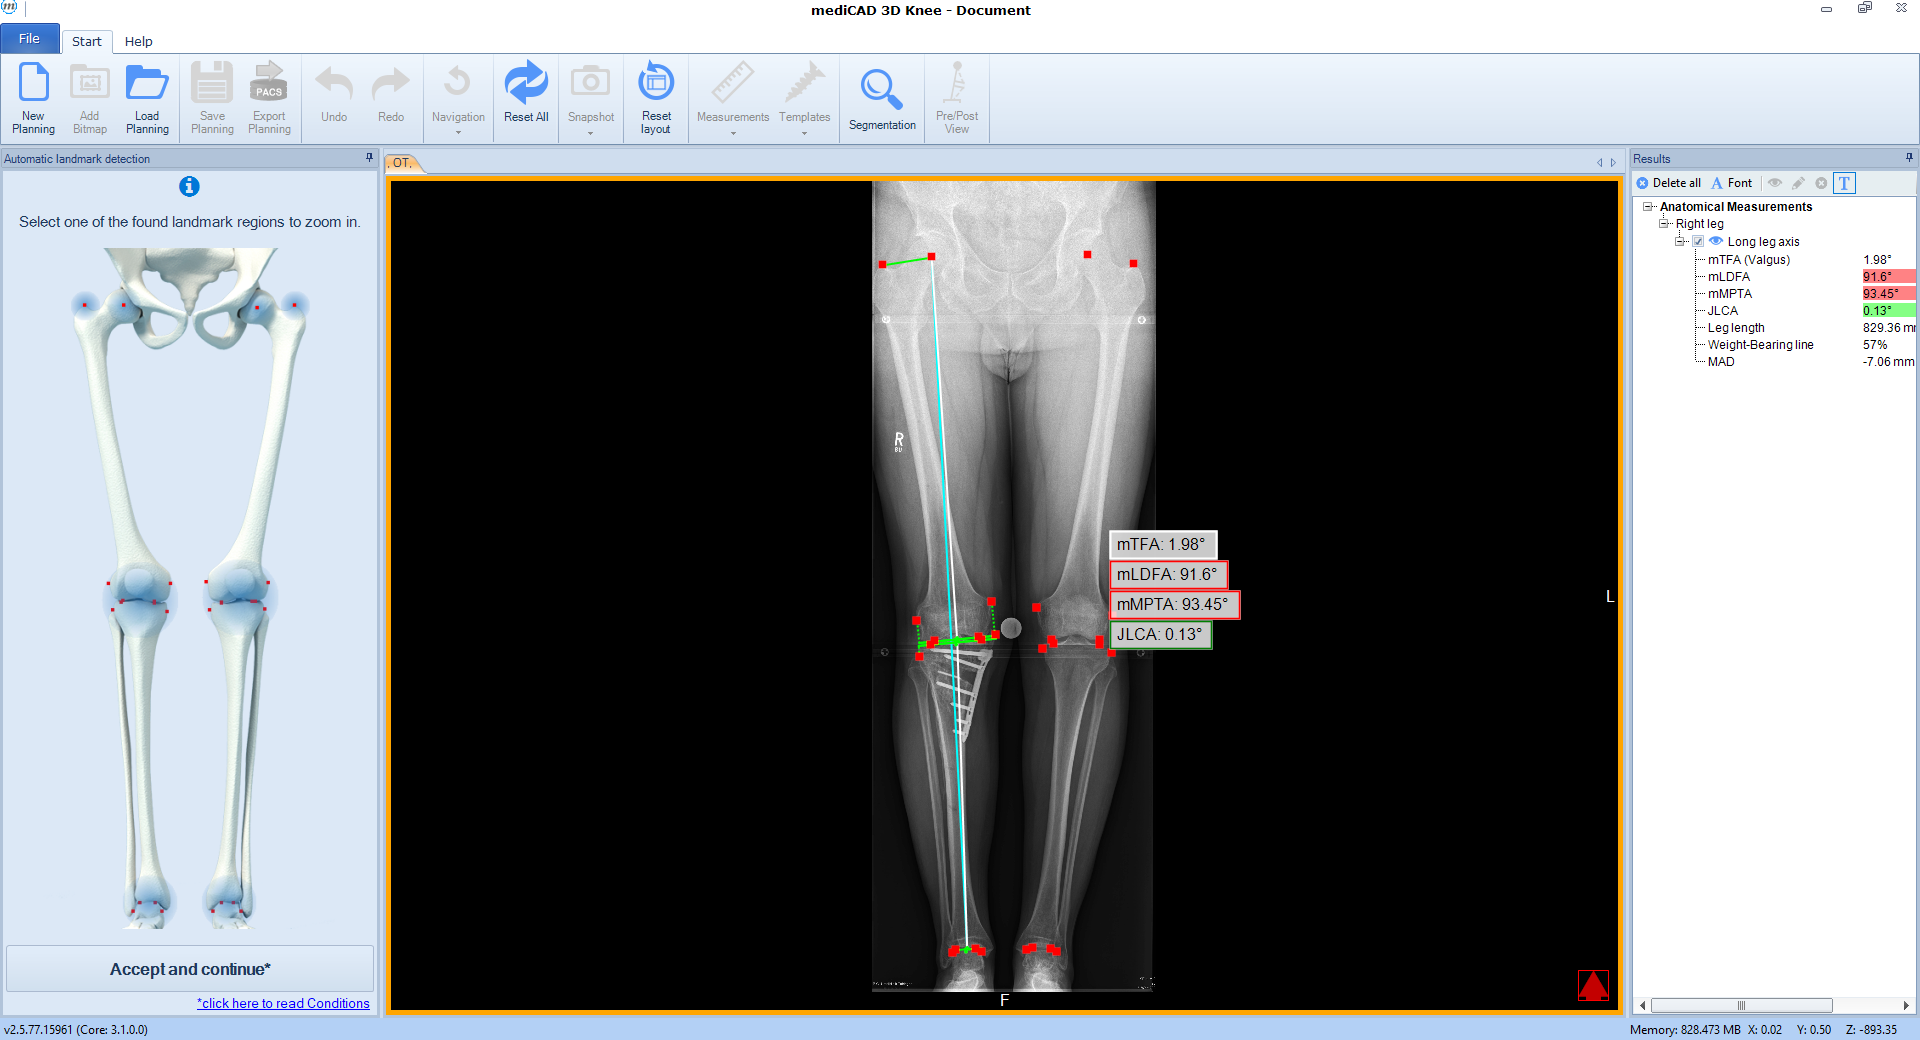

The software automatically detects all necessary landmarks (Fig 1). Based on their position (which can be adjusted manually) the software calculates all essential values (axis, joint lines, and angles) and delivers a detailed report. A traffic light system illustrates normal, intermediate, or pathological values.

Following the deformity analysis, the software automatically recommends a surgical procedure, eg, medial opening wedge high tibia osteotomy, depending on the type of deformity (Fig 2). The user can follow the proposed procedure or choose individual options.

A 52-year-old man with a posttraumatic deformity 2 years after tibial plateau fracture AO/OTA 41C3.3e, PL, PM complained of pain after a normal working day. The patient was a heavy smoker. Activities like sports or hiking were discontinued. Surprisingly ligaments in the coronal and sagittal planes were stable. There was no effusion. Pain was localized in the medial compartment. The range of motion was limited to 0/0/130°. The deformity was corrected with a high tibial osteotomy.

Showcasing a high tibial osteotomy case